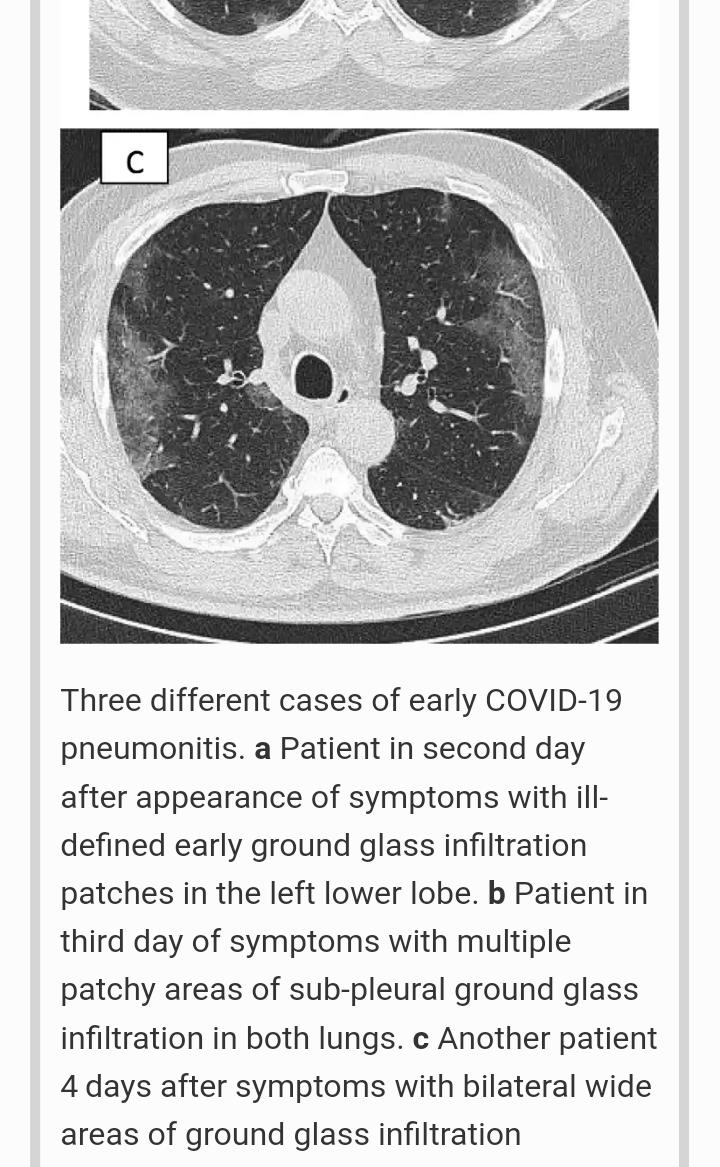

The typical appearance of COVID-19 pneumonia is bilateral patchy areas of ground glass infiltration, more in the lower lobes. The appearance of other signs like consolidation, air bronchogram, crazy pavement appearance, and air bubble signs appear during the course of the disease.

Ground glass opacity (GGO) is the non-specific hazy opacification of the lung in the X-ray or computed tomography with no obliteration of bronchial or vascular markings. The presumed pathology include partial filling of the lung alveoli by fluid, interstitial thickening, or partial collapse of lung alveoli

They are heterogeneous, some micro area opacified whereas the adjacent micro area not so,and hence the picture is percieved of that of tiny pieces of ground glass.

The early stage is characterized by dilatation of capillaries and engorgement of vessels, mild fluid exudates in the alveoli, and interstitial edema, resulting in single or multiple patchy ground glass opacities. The ground glass opacities are mostly peripheral and subpleural.